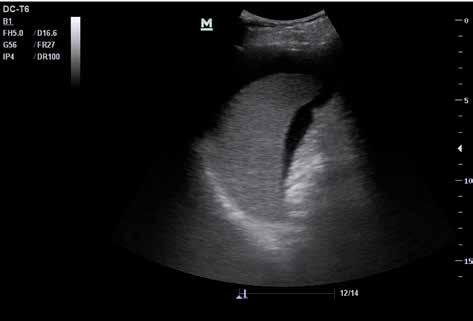

Abb. 34 ˘ Morison-Pouch (1) zwischen Leber (2) und rechter Niere (3). Rechtsseitiger Flankenschnitt 1 2 3

Zunächst sammelt sich mögliche freie Flüssigkeit an drei typischen präformierten Stel len im Bauchraum und kann hier sonografisch dargestellt werden. Dies sind der MorisonPouch, der Koller-Pouch und der Douglas-Raum (von engl. „Pouch“ für „Beutel“, Abb. 34 –36).

Der Morison-Pouch ist eine Aussackung des Peritoneums zwischen Leberunterrand und rechter Niere. Dem entspricht auf der Gegenseite der Koller-Pouch zwischen Milz und linker Niere. Der Douglas-Raum befindet sich dorsal hinter der Harnblase und zieht bis ins kleine Becken.

Abb. 37 ˘ Freie Flüssigkeit (FAF) (1) im Morison-Pouch. Rechtsseitiger Flankenschnitt Abb. 38 ˘ Freie Flüssigkeit (FAF) (1) im Koller-Pouch. Linksseitiger Flankenschnitt